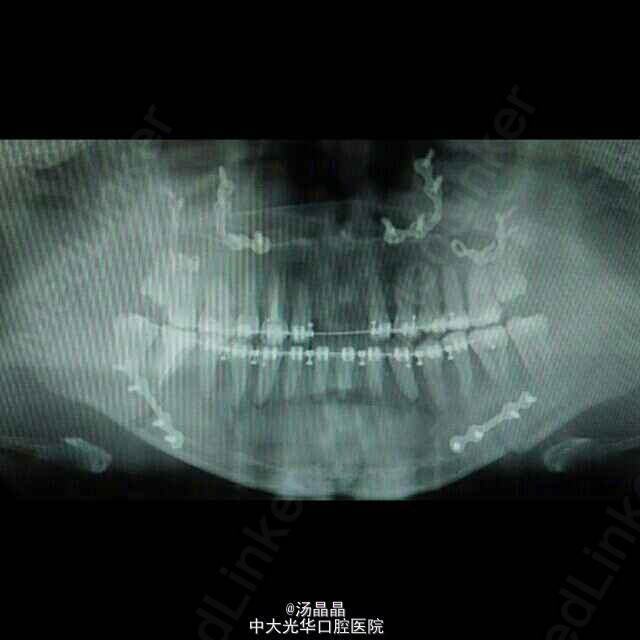

上颌前突,下颌后缩,治疗为:全麻下行上颌lefort I型截骨前徙术,BSSRO后退术,双侧下颌骨去骨皮质术,骨内坚固内固定术

口内创口缝线固定良好,上下颌咬合可,口内卫生可,勿咬硬物